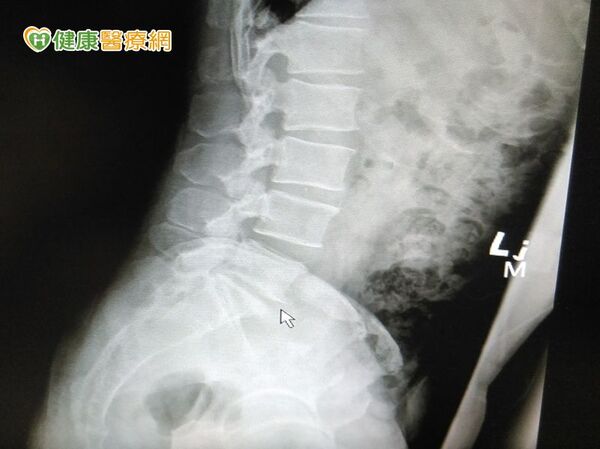

經醫師檢查,發現患者第五腰椎和第一薦椎椎間盤突出合併脊椎移位,安排脊椎精準微創融合手術後,患者脊椎狀況回復穩定,目前也已恢復日常生活;童綜合醫院微創中心副院長徐少克指出,術中切除突出的椎間盤,且放入人工椎間盤支架,將移位部位復位,手術流血量未超過100cc,術後恢復良好。